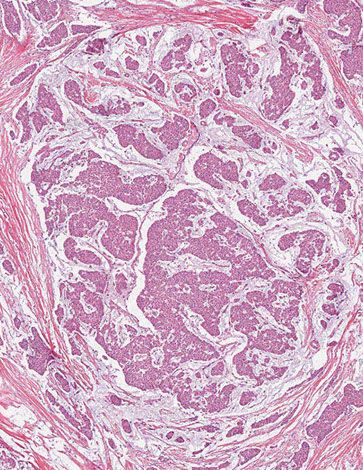

Histo: Periductal stromal hypercellularity (and periductal stromal heterogeneity, having areas with more hypercellular stroma and areas with more hypocellular stroma) and prominent intracanalicular growth pattern

- Maple-leaf appearance from stroma juttin into cystic spaces

Malig potentional based on stromal cellularity, stromal atypia, stromal mits, tumor margin, stromal overgrowth (one 4x field of pure stroma, no epithelium) - all are subjective